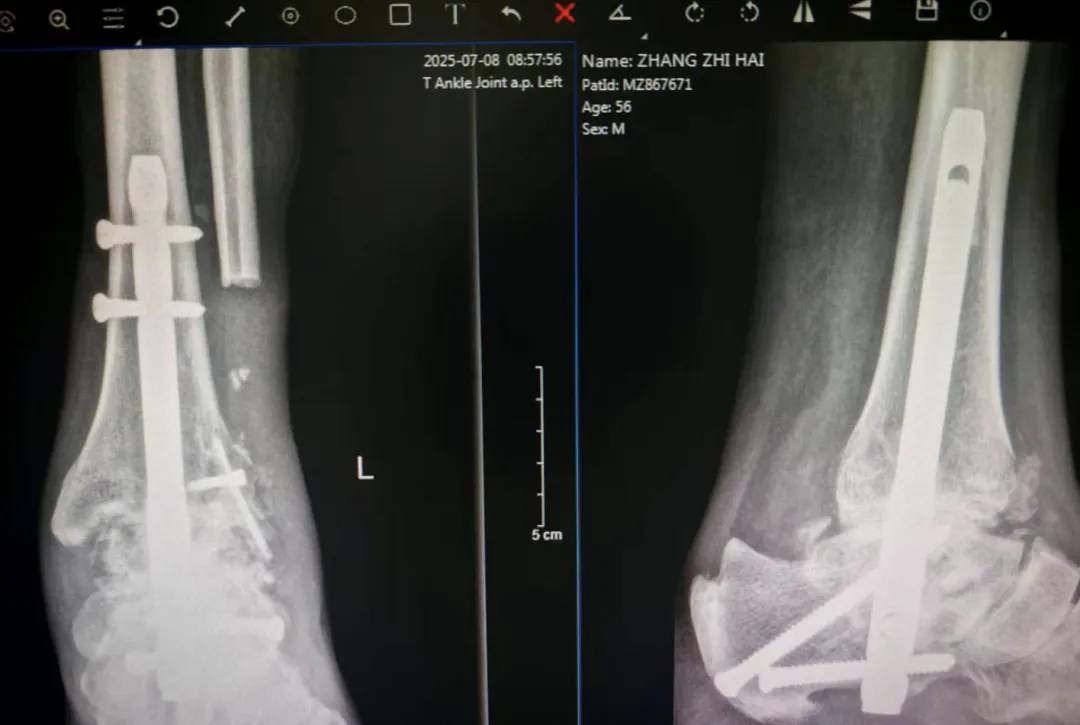

▲术后2月复查,X片显示关节已有融合迹象

骨科足踝专业小组张彬、张志伟两位主治医师经过共同研讨,决定采用先进的逆行髓内钉技术进行胫骨与跟关节融合手术,并成功实施。术后5个月回访,患者表示,走路再无疼痛感,已能够完全脱拐行走,正常参与社交活动和日常出行,生活质量得到显著提升。